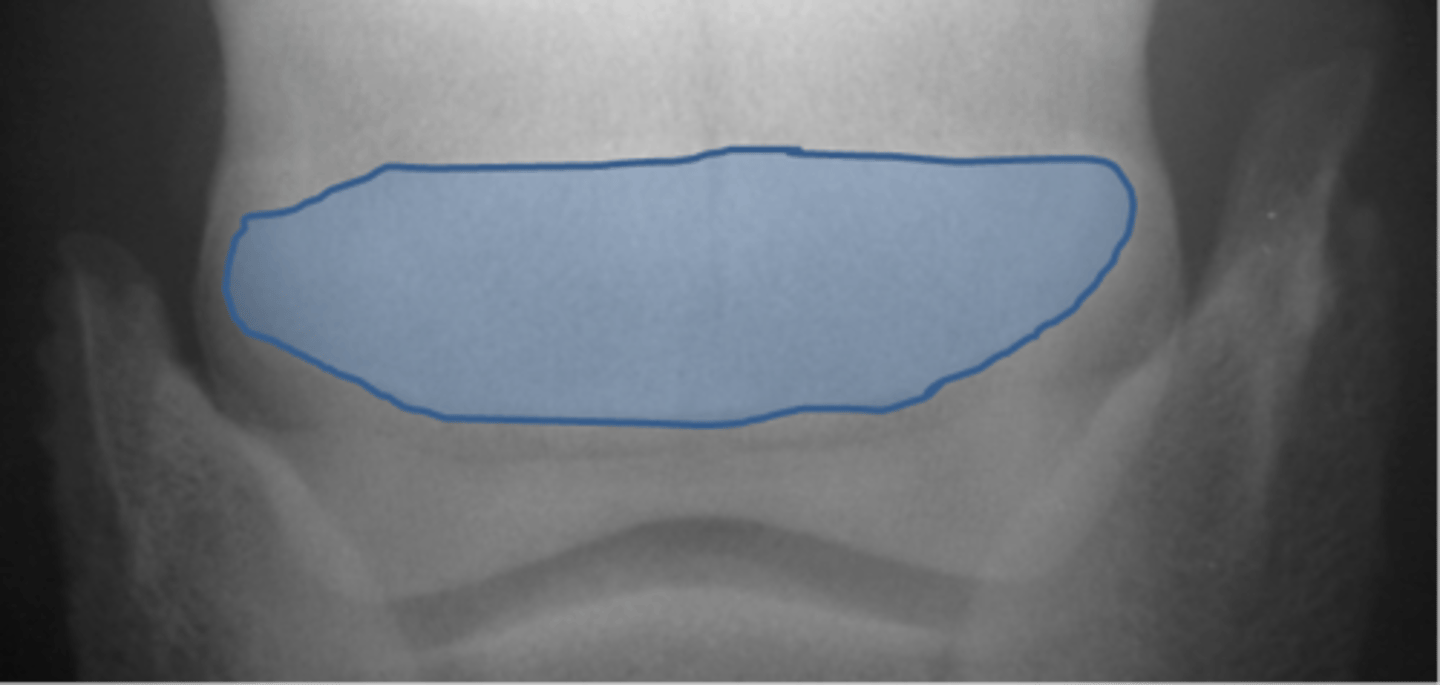

Navicular bone

Flexor cortex

Navicular bone

Proximal border of navicular bone

Distal border of navicular bone

Synovial invaginations

Flexor skyline

What view is this?

1. Flexor surface

2. Corticomedullary distinction

3. Number of synovial invaginations

What is the flexor skyline used to evaluate?

Navicular bone

Articular surface of navicular bone

Flexor surface of navicular bone

Sagittal ridge

Synovial invaginations